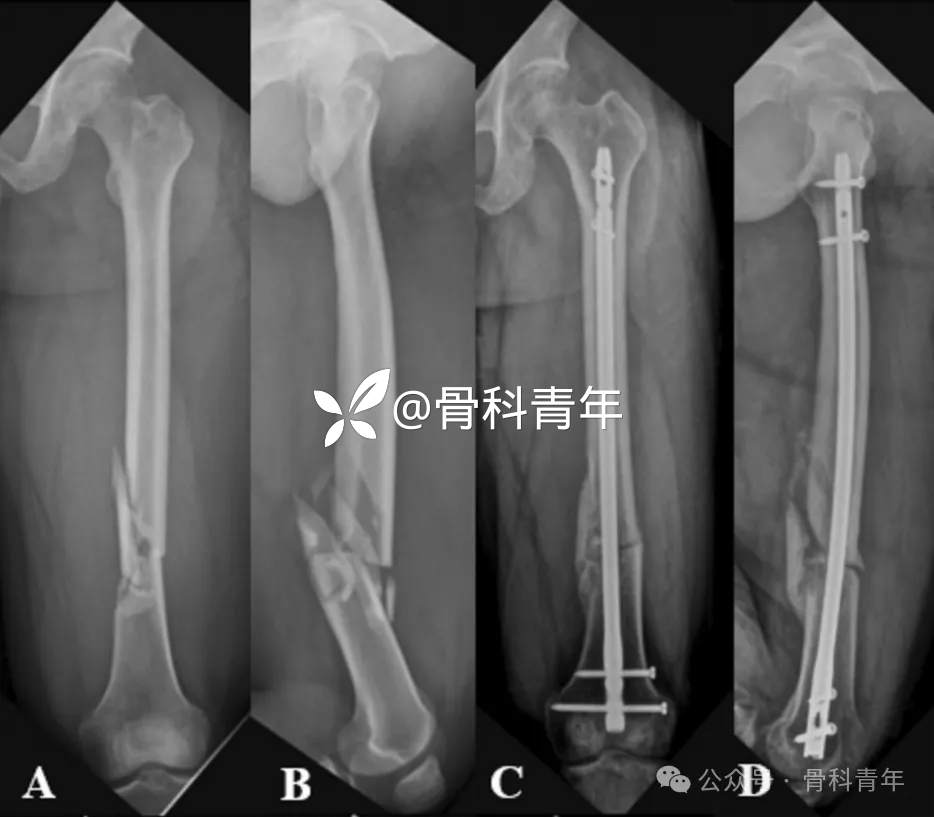

▲ 病例1:55岁男性,车祸外伤,X线提示股骨干骨折(A.B);行髓内钉内固定术后9月,可见骨折断端萎缩,骨折间隙清晰,骨断端硬化,考虑萎缩性骨不连(C.D);更换粗髓内钉后(E.F),术后14月(G.H)仍可见骨折断端无明显连续性骨痂形成。